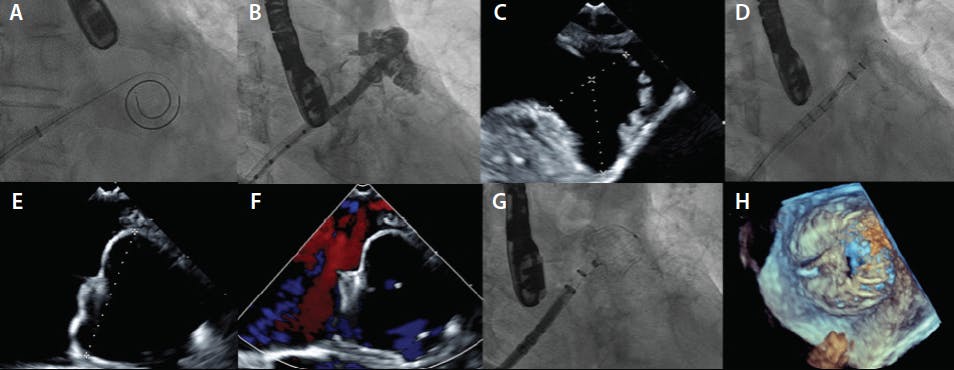

Both pre- and periprocedural cardiac imaging are of paramount importance in LAAC (Figure 2). Traditionally, the imaging technique of choice has been TEE due to its ability to obtain high-quality images of the LAA in real-time. However, there are some downsides to TEE, including the need for sedation or general anesthesia and more recently, reluctance to perform aerosolizing procedures during the COVID-19 pandemic. Cardiac CT has emerged as a reasonable or even preferable alternative to TEE in pre-LAAC planning. In fact, a number of studies have shown that LAA sizing on CT is more accurate23-25 and is exceptionally good at ruling out preexisting LAA thrombus.26,27 During the procedure, imaging guidance with intracardiac echocardiography (ICE) is increasingly used instead of TEE because general anesthesia can be avoided. Although manipulation of the ICE catheter to obtain good images may be difficult at times, overall success rates, laboratory time, and cost appear similar to TEE-guided procedures.28,29

Figure 2. Procedural imaging—TEE and fluoroscopy. Crossing the interatrial septum using the VersaCross RF wire (A). Contrast injection of the LAA with pigtail catheter (B). Measurement of the LAA on TEE (C). Advancing the Watchman FLX into position (D). Measurement of the Watchman FLX at maximal diameter after deployment; should have 10%-30% compression (E). Color flow Doppler to rule out significant peridevice leak (F). Deployment of Watchman FLX in the LAA (G). Three-dimensional imaging on TEE (H).